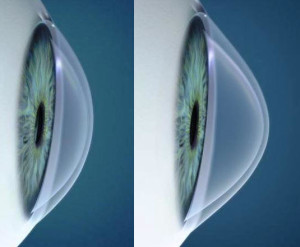

O ceratocone é uma doença ocular que afeta diretamente a córnea — a lente transparente que recobre a parte frontal do olho. Quando essa estrutura começa a afinar e se projetar para frente, assumindo o formato de um cone, a visão fica distorcida e embaçada.

O ceratocone é uma doença progressiva e não inflamatória da córnea. Sua principal característica é o afinamento gradual e a deformação dessa estrutura, o que leva à sua curvatura irregular, dificultando a passagem correta da luz até a retina. A condição costuma surgir na adolescência ou no início da vida adulta e pode evoluir de forma variável.

O anel intraestromal é um pequeno implante semicircular inserido no interior da córnea. Sua função é regularizar a curvatura corneana. Sendo assim, ele não interrompe a progressão da doença, mas melhora a geometria da córnea e, com isso, a qualidade visual.

Diferente do crosslinking, que busca estabilizar a doença, o anel é um tratamento voltado à reabilitação visual. Ele pode permitir, inclusive, o uso de óculos ou lentes gelatinosas em casos em que antes só era possível o uso de lentes rígidas ou esclerais.